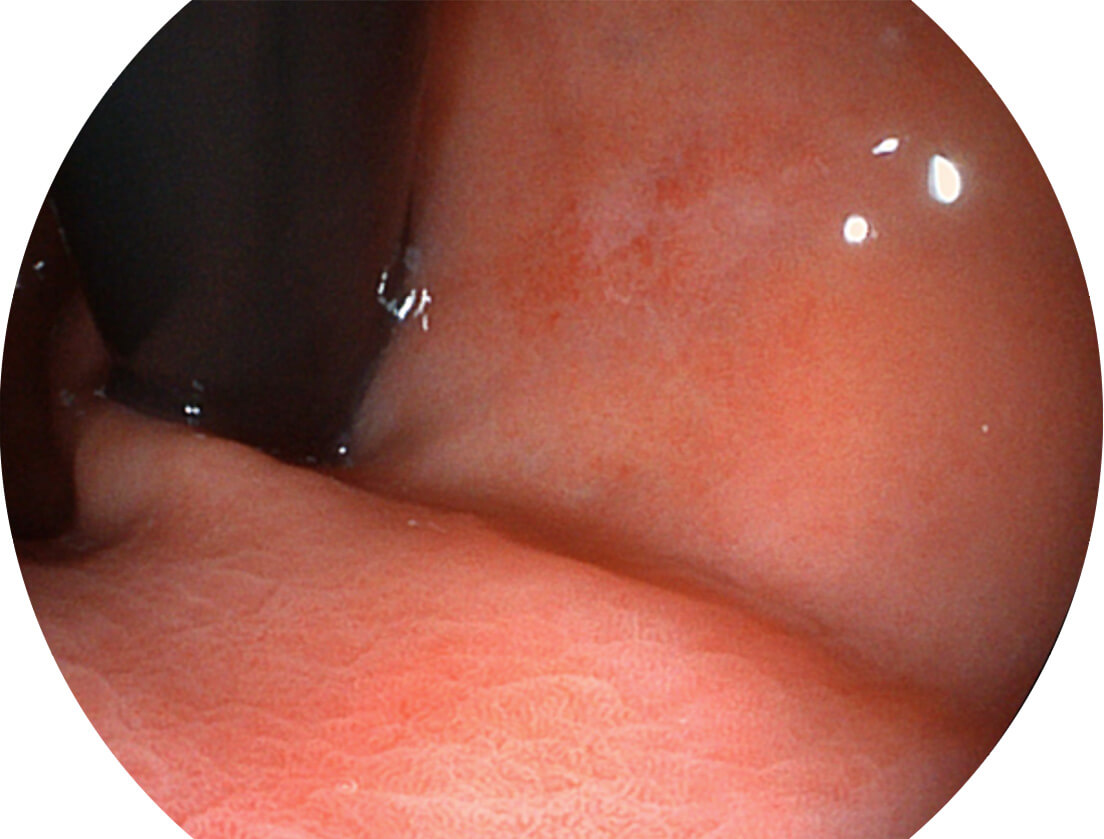

送水方向与手术器械方向,两者更贴合,能快速冲洗黏膜表面的粘液及出血,发现病变和出血点。